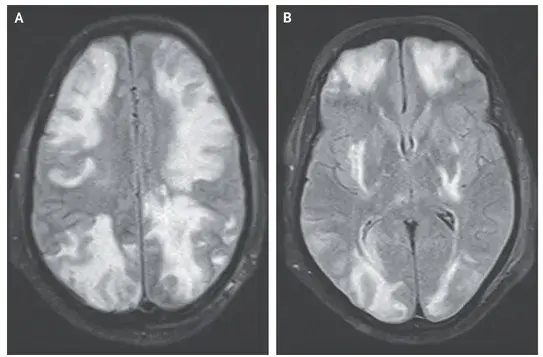

Por que é tão importante avaliar sódio em urina de 24h na DRC?

Por que é tão importante avaliar sódio em urina de 24h na DRC?

Avaliação do sódio em urina de 24 horas pode fornecer inúmeras informações ao nefrologista. Confere esse estudo.